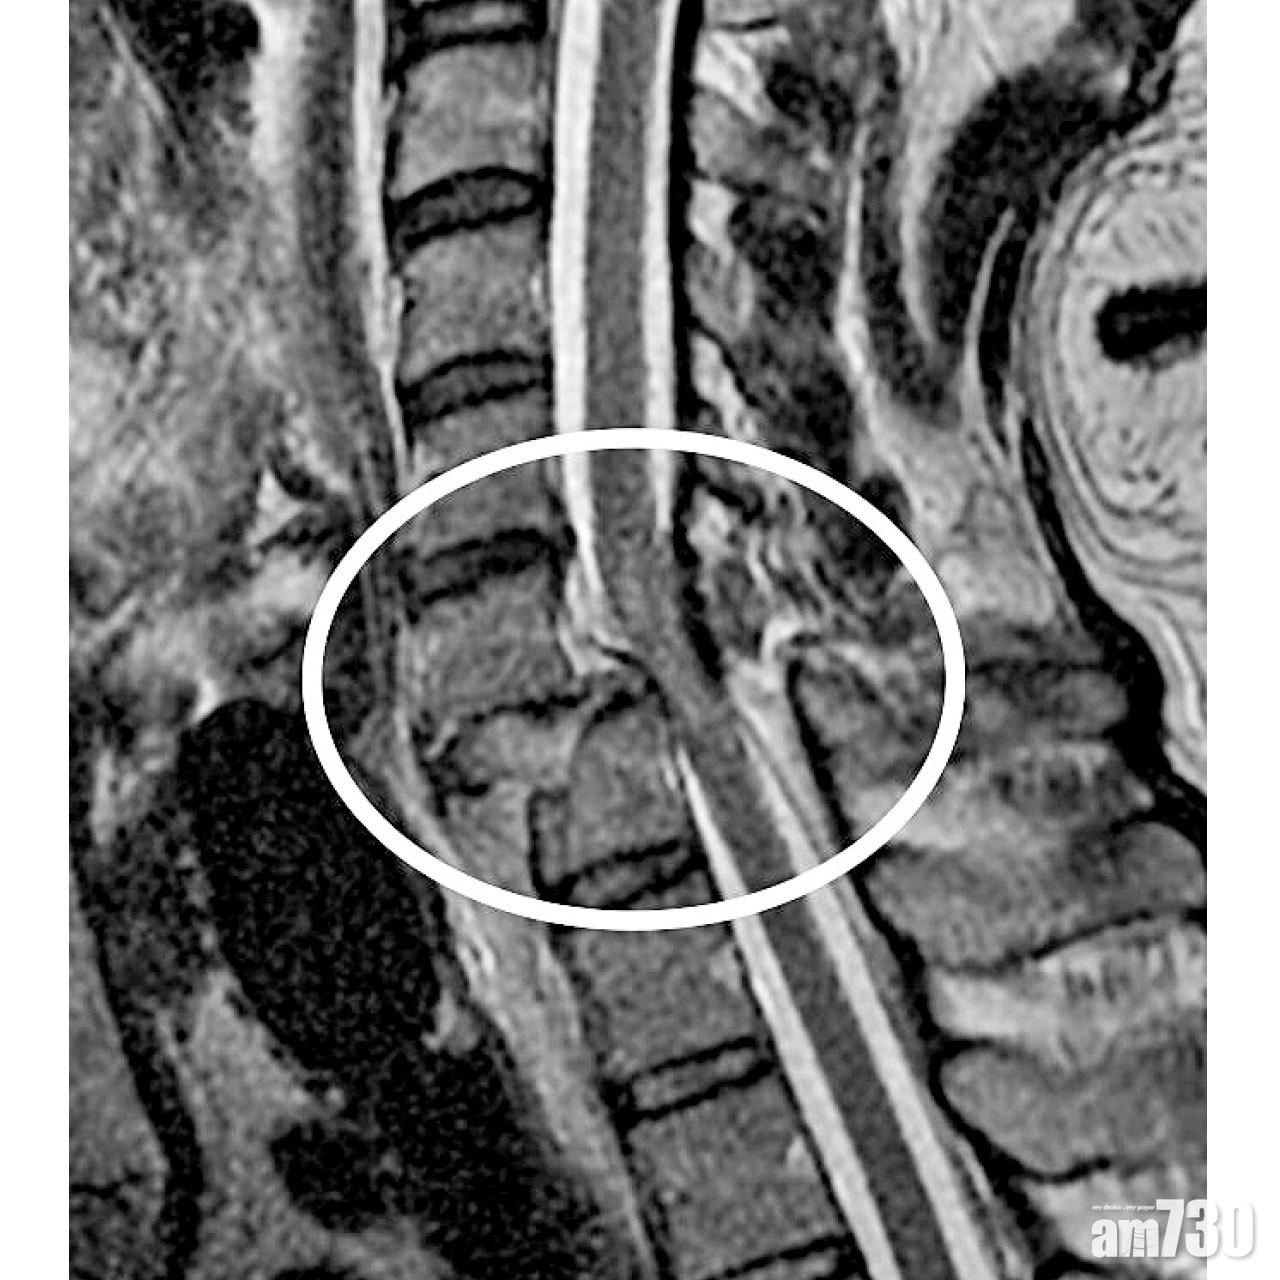

至於造成四肢癱瘓(Tetraplegia)的創傷成因,除了交通意外,還包括傷者習以為常的「離地」動作,如爬梯工作或體操運動。倘若不慎失足並頭部着地,所帶來的衝擊力,不但可造成頸椎骨折並移位,還瞬間令頸椎內的脊髓受損。

脊髓是大腦連繫軀幹與四肢的「命脈」,一旦受損,便不能傳達大腦與四肢之間的神經訊息,四肢亦不再聽從中央的指揮,令身首無法回復到「We Connect」的狀態。根據美國脊髓損傷協會的定義,脊髓損傷可分為五個級別。傷者的四肢可以是完全或非完全地失去運動與感覺功能,甚至會出現大小便失禁,嚴重者更須靠呼吸機維持生命。

當傷者的生理機能穩定下來,骨科醫生會盡快安排照磁力共振來評估傷勢,並做頸椎減壓及融合術。頸椎骨折得以固定後,傷者便可盡快離床接受復康治療,免得臥床日久,帶來肺炎或褥瘡等可致命的併發症。醫學界至今仍未研發出,能令脊髓完全損傷者恢復運動功能的治療。雖然外骨骼機械人技術,能輔助傷者站立與行走,但因價格高昂而仍未普及。至於脊髓非完全損傷者,四肢肌力都會在術後首年內,在復康治療下有所改善。部分傷者可以重新站立行走,或是操控電動輪椅,自由地出入社區。